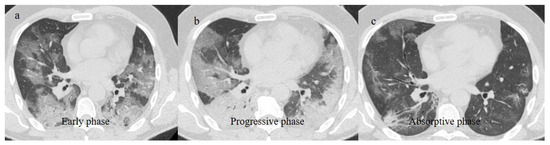

- Wang, Y.; Dong, C.; Hu, Y.; Li, C.; Ren, Q.; Zhang, X.; Shi, H.; Zhou, M. Temporal Changes of CT Findings in 90 Patients with COVID-19 Pneumonia: A Longitudinal Study. Radiology 2020, 296, E55–E64. [Google Scholar] [CrossRef]

- Hu, Q.; Guan, H.; Sun, Z.; Huang, L.; Chen, C.; Ai, T.; Pan, Y.; Xia, L. CT features and temporal lung changes in COVID-19 pneumonia in Wuhan, China. Eur. J. Radiol. 2020, 128, 109017. [Google Scholar] [CrossRef]

- Li, X.; Zeng, W.; Li, X.; Chen, H.; Shi, L.; Li, X.; Xiang, H.; Cao, Y.; Chen, H.; Liu, C.; et al. CT imaging changes of corona virus disease 2019(COVID-19): A multi-center study in Southwest China. J. Transl. Med. 2020, 18, 154. [Google Scholar] [CrossRef]